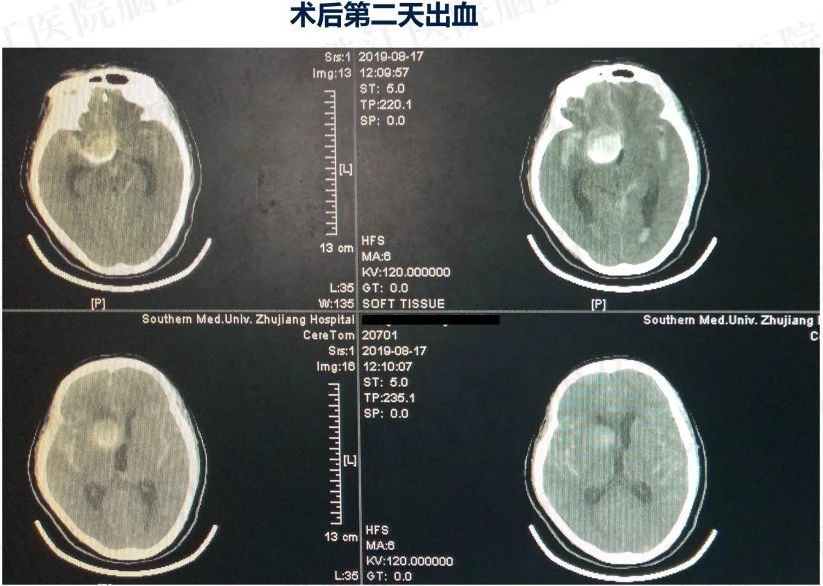

患者入院后造影发现“颈内动脉床突上段巨大动脉瘤,大小约2.7x3.5cm。决定行PIPELINES密网支架植入治疗。

晚上急诊造影